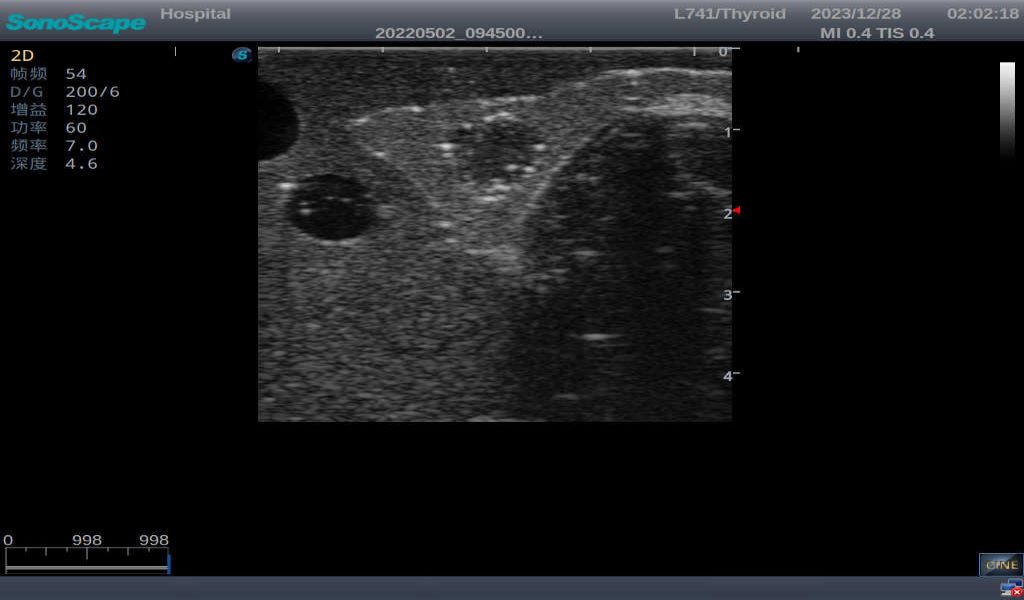

3)       It comes with four (4) thyroid modules and can show five (5) ultrasonic images: normal thyroid, thyroid adenoma, thyroid cancer, nodular goiter, thyroid cyst

Thyroid adenoma with well-defined border and smooth uniform halo

Nodular goiter with irregular border and varying sizes of low echo, isoechoic, or high echo nodules